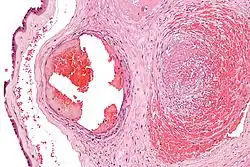

| Intermediate magnification micrograph of the placental disc showing a thrombosed fetal vein, as may be seen in fetal thrombotic vasculopathy. H&E stain. | |

Fetal thrombotic vasculopathy is a chronic disorder characterized by thrombosis in the fetus leading to vascular obliteration and hypoperfusion.

It can be diagnosed by histomorphologic examination of the placenta and is characterized by fetal vessel thrombosis and clustered fibrotic chorionic villi without blood vessels.